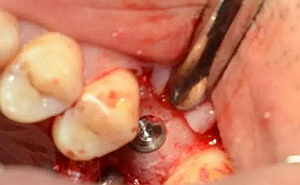

局麻后切開(kāi)翻瓣

暴露骨面,輕柔處理軟組織

清理骨面和臨牙齦下結(jié)石及炎性肉芽組織

定點(diǎn)定向,初步擴(kuò)孔

使用止停環(huán)控制深度,逐級(jí)預(yù)備打開(kāi)嵴頂入路。探之竇膜力反饋正常,呈持續(xù)張力。手動(dòng)探查分離通路周圍竇粘膜并略提升。

植入種植體,注意方向控制和初期穩(wěn)定性。

上覆蓋螺絲